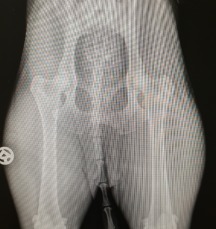

Heute haben wir die offizielle GRSK Gutachter Auswertung unserer Lillyfee (Senta VDB x Deacon VDB) wiederbekommen.

Wir freuen uns riesig, unsere Lillyfee ist

HD A und ED 0